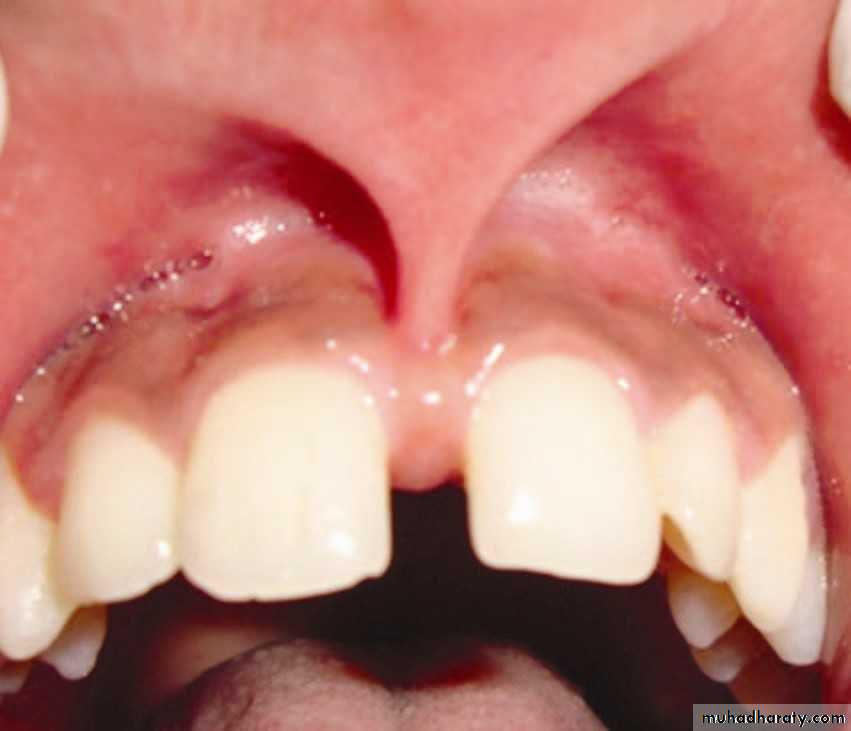

Abnormal labial Frenum If the frenum is thick, itprevents the closure of diastema (which is normal during mixed dentition prior to the eruption of canines)In these cases a frenectomy is indicated11-TRANSPOSITION:- An abnormality where the position of teeth is interchanged- The most transposed teeth: The maxillary canines & first premolars